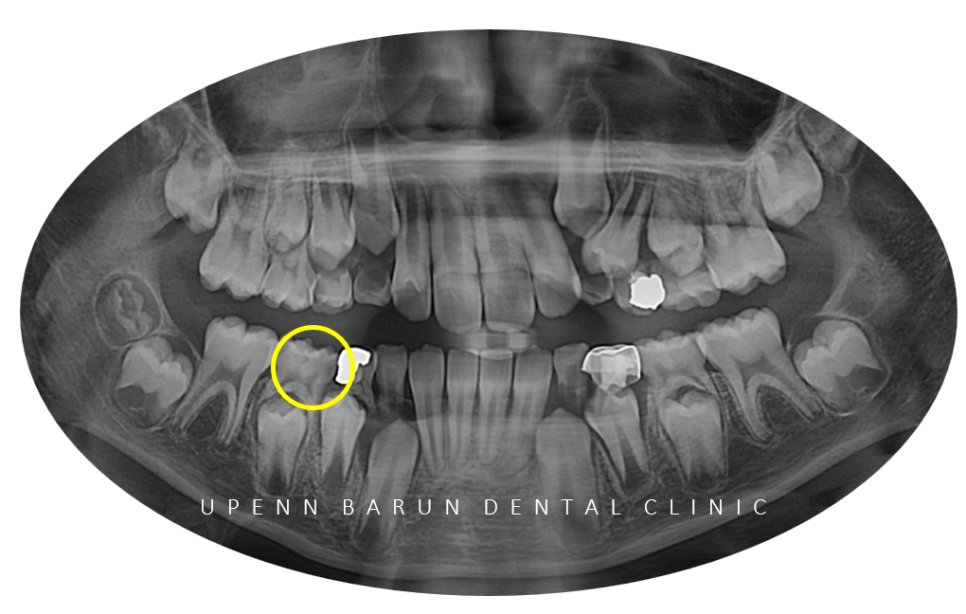

잠실인비절라인교정을 진행하기 전!

엑스레이를 확인해 보니

우측아래 눈에 띄게 까맣게 충치가 있어

충치치료를 마무리 해드리고 교정을 진행해 드렸습니다.

교정부터 충치치료까지 한병원에서 치료가 가능한

유펜바른치과에서

교정을 시작해야 하는 이유!!

눈치채셨나요? ㅎㅎ